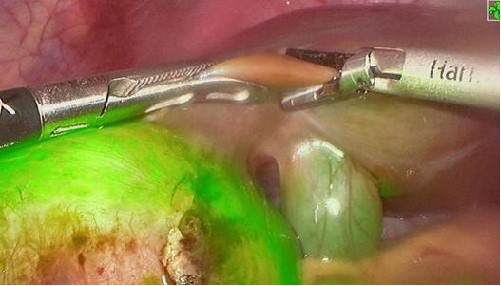

PL002是浙江普利药业有限公司研发的荧光/磁共振双模态造影剂,荧光/磁共振双模态造影剂的成功研发将成为提高脑胶质瘤手术效率的有效方案。术中荧光技术与核磁共振成像的结合,相较于单独使用,能够更准确地识别肿瘤组织与功能区的位置关系,以及患者的肿瘤浸润边缘。这种联合使用不仅能在保留患者功能的前提下实现功能区脑胶质瘤的最大限度安全切除,还能有效降低术中神经损伤的风险。

去年10月,PL002已经获得FDA签发的美国药物临床试验批件,用于原发性肝癌患者的术前诊断及术中导航。此次在国内申报的适应症为脑胶质瘤患者的术前诊断及术中导航。相较于原发性肝癌,脑胶质瘤对于切除精度要求更高,尤其是临近重要功能区的时候,因此对精准诊断的造影剂的临床需求更为迫切。